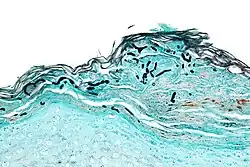

Micrograph of a superficial dermatomycosis. The fungal organisms are the dark staining, thick, quasi-linear objects below with skin surface. Vulvar biopsy. GMS stain. | |